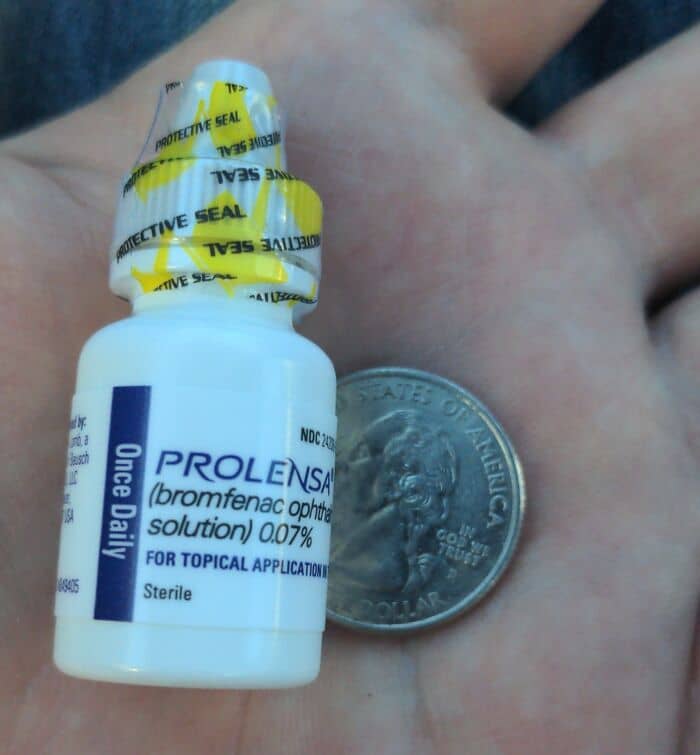

#39 Healthcare In The USA: $396 Bottle Of Eye Drops My Dad Needed Before Cataract Surgery